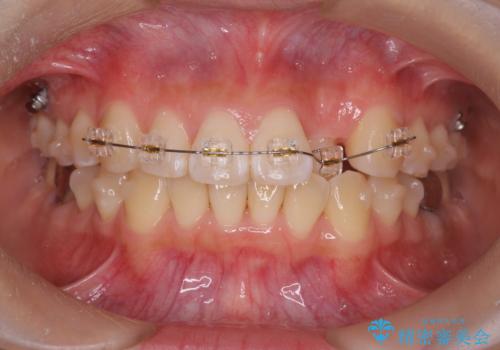

正中のズレ、引っ込んだ前歯の矯正

- 噛んだ時の前歯正中のズレ、引っ込んでいる前歯を治したい。と矯正治療を希望され来院されました。

左上2の前歯はスペースが足りないため、後方に引っ込んでしまっている状態です。

マウスピース矯正システムインビザラインで歯の後方移動、咬合関係の修正を行ったのち、引っ込んでいる左上2をワイヤーを用いて短時間で引き出す治療計画としました。

部分ワイヤー矯正を行なったことで約3ヶ月という短期間で前歯を綺麗に並べることができました。